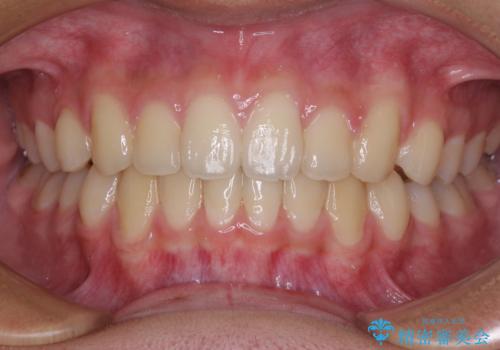

隙間の空いた歯列とボロボロの乳歯 インプラント治療と矯正治療

歯列はワイヤー矯正にて改善することとしましたが、上下歯列にも隙間があったので、舌の突出癖を改善するトレーニングを徹底的に行うこととしました。

舌の突出癖改善のトレーニングが全くうまくできず、治療期間が長期化しました。

早く治療を終えたいとの要望があり、トレーニング次第と伝えるとようやく練習をするようになり、その後は速やかに上下の隙間が改善されました。